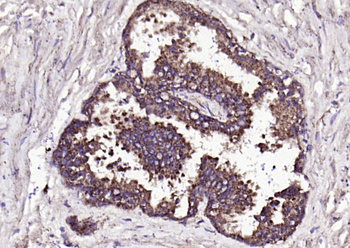

产品细节图片2

Fixative-fixed, paraffin embedded (human prostate), Antigen retrieval by boiling in sodium citrate buffer (pH6.0) for 15 min, Block endogenous peroxidase by 3% hydrogen peroxide for 20 minutes, Blocking buffer (normal goat serum) at 37°C for 30 min, Antibody incubation with (FGF8) Polyclonal Antibody, Unconjugated (orb10653) at 1:200 overnight at 4°C, followed by operating according to SP Kit (Rabbit) instructionsand DAB staining.